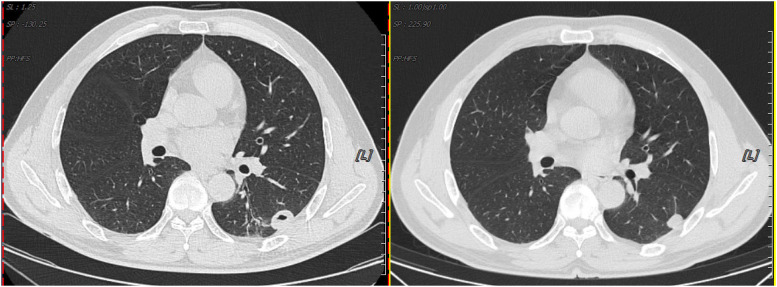

Results: Most patients in the PC group are male (59.6%), with an average age of 49.4 years. Most of the patients have no underlying disease (51.9%). Diabetes and hypertension are the most common comorbidities. Most patients (53.8%) are asymptomatic. Cough and sputum are the most frequent clinical symptoms, followed by fever and chest distress. Nodules and exudative consolidation are the most common imaging findings, and the culture positivity rate is 25%. Forty patients are positive according to the BALF GXM test, for a positivity rate of 83.3% and a negative predictive value of 91.8%. Moreover, 39 patients are positive according to the serum GXM test, for a positivity rate of 81.3% and a negative predictive value of 90.9%. The positivity rate for serum plus BALF is 95.8%. There is no significant difference (P > 0.05) in diagnostic value between BALF and serum GXM tests for PC. GXM positivity rates differ significantly among paired BALF, serum, and BALF plus serum groups (P < 0.05).

Abstract Image